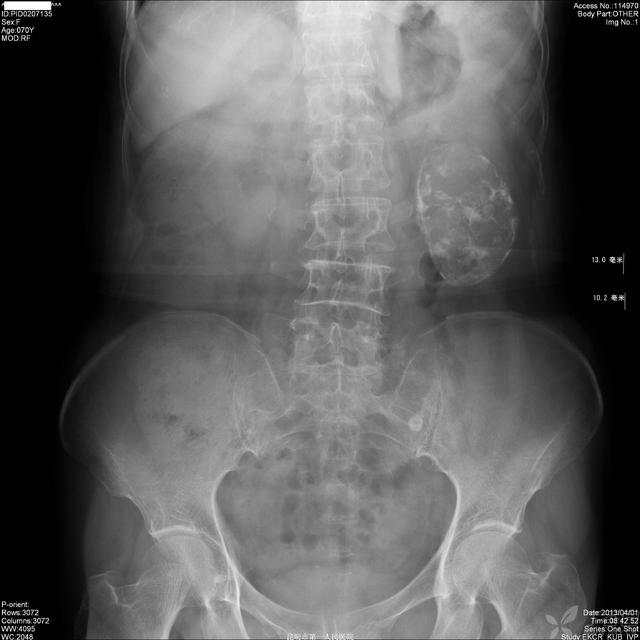

图1,KUB:

img

X线:左肾下极肿块,边界光滑,多发点片状钙化灶,左肾下肾盏受压移位、拉长、变形,肾盂输尿管上段未受侵犯。